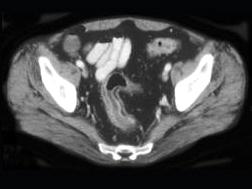

问题 男,35岁,腹痛、腹泻、腹胀、脓血便、里急后重,结合图像,选择最可能诊断 ( )

选项 A、假膜性肠炎 B、结肠淋巴瘤 C、结肠克罗恩病 D、结肠结核 E、溃疡性结肠炎

答案 E